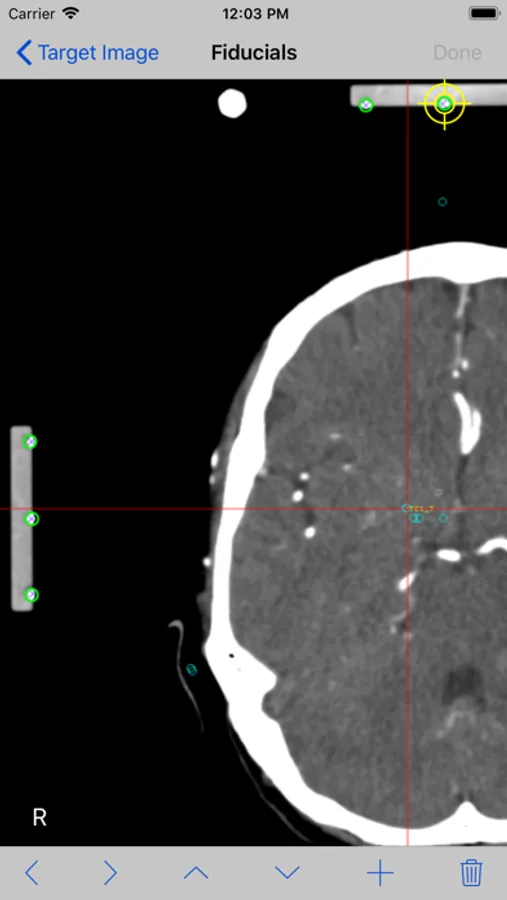

7. Mark each fiducial on the image. StereoCheckRM use nine (9) fiducials. Tap the Done button.

8. Mark the target point you want to reach and tap the Done button.